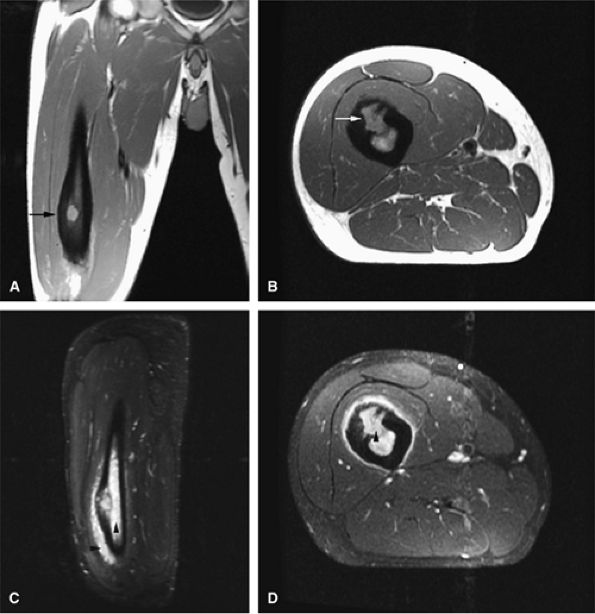

FIGURE 14-14 ● Cortical osteoblastoma of the femoral diaphysis. Coronal (A) and axial (B) T1-weighted images show osteoblastoma isointense to muscle with adjacent cortical thickening (arrows). Reactive bone marrow edema is hyperintense on sagittal (C) and axial (D) fat-suppressed T2-weighted fast spin-echo images (arrowheads).